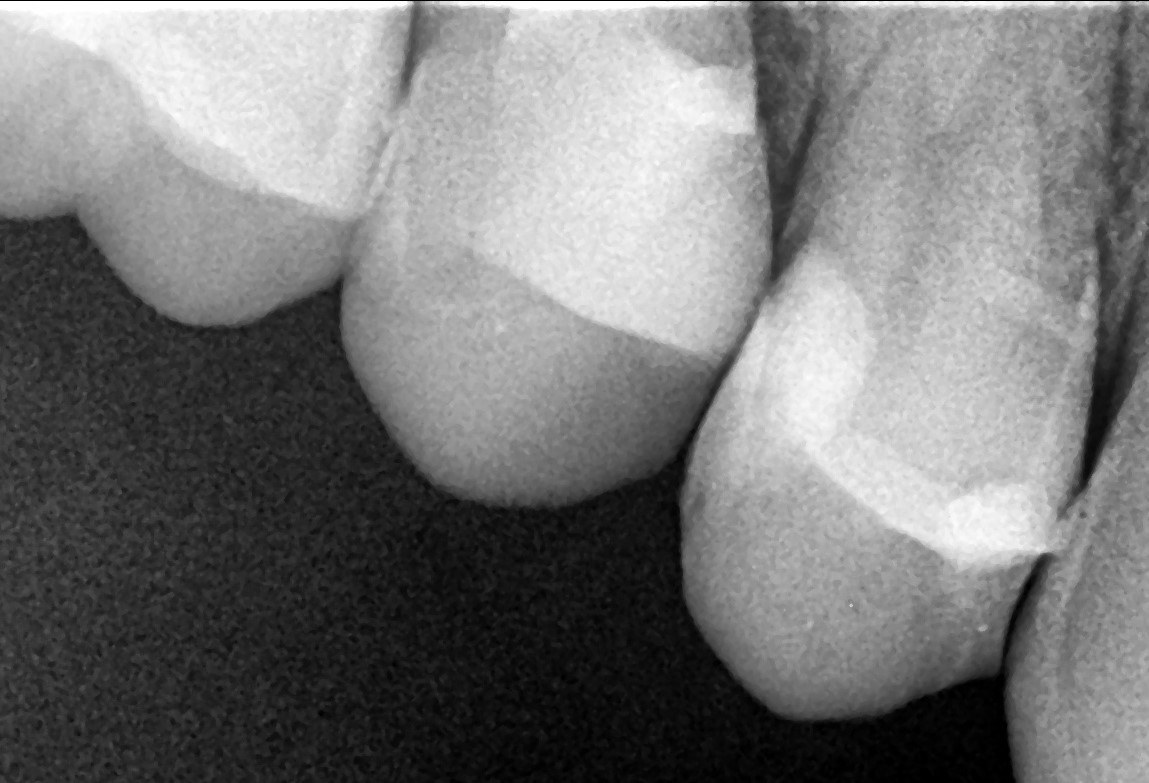

• In the palatal canal, the 10/07 “Opener” file from the SuperSystem Advanced Kit was used at 250 rpm and 1.5 Ncm torque, progressing to the middle third.

Following irrigation, 17/05 file was used at the same settings to reach the apex.

Working length was confirmed using a #06 K-file.

Canal enlargement was completed with the Perfect Advanced Kit 17/05 file (images 3 and 4).